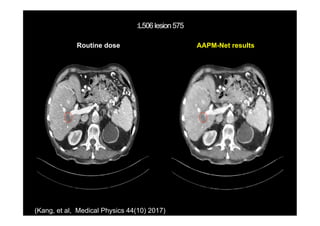

(Kang, et al, Medical Physics 44(10) 2017)

Routine dose AAPM-Net results